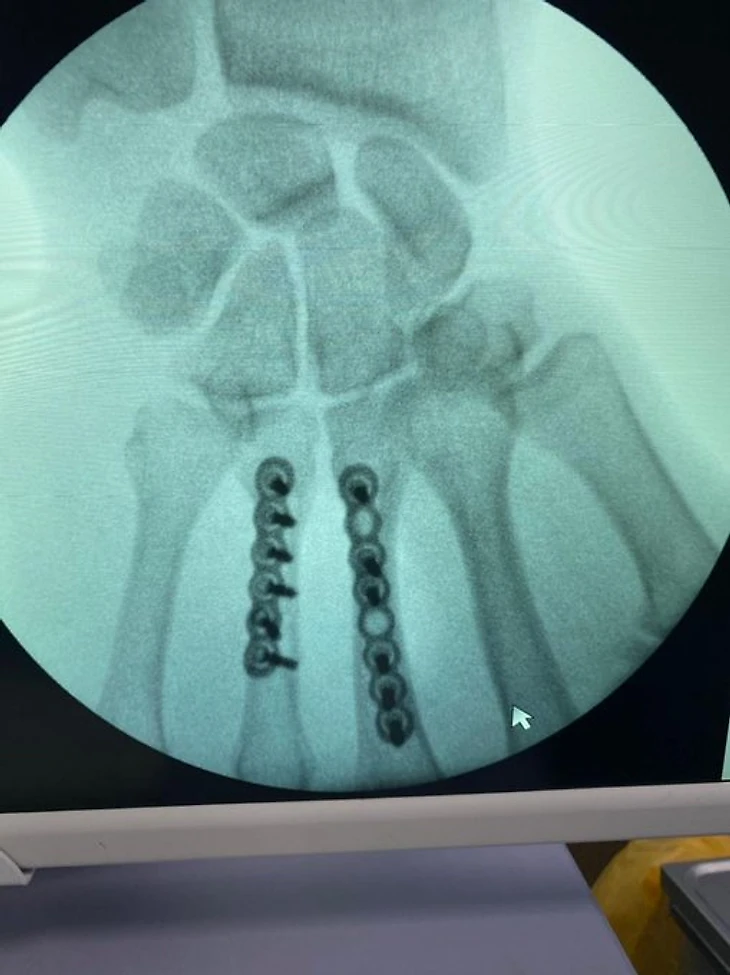

— Закрытый неосложнённый винтообразный перелом диафизов третьей и четвёртой пястных костей правой кисти со смещением отломков. Именно смещение и стало показанием для операции.

Если бы Непряева не была спортсменкой, мы проводили бы операцию иначе: скрепили бы отломки не пластинами, а винтами. При длинной плоскости перелома технология предполагает именно это. Но так как очевидно, что Наташа будет нагружать руку не как обычный человек, а в гораздо большей степени, для более прочной и надёжной фиксации было решено скреплять сломанные кости пластинами. Это, помимо всего прочего, позволяет человеку гораздо быстрее вернуться в строй.

Сергей Астахов твиттер : Так выглядит рука Натальи Непряевой после сложной операции. Сломанные пальцы собирали в течение часа.

Наталья Непряева @natali_nepryaeva прооперирована в АНО ЦКБ Святителя Алексия Митрополита Московского, руководителем центра микрохирургии кисти, реконструктивной и пластической хирургии, к.м.н., доцент кафедры травматологии и ортопедии РНИМУ им. Пирогова - Калантырской Валентиной Анатольевной.Была выполнена реконструкция пястных костей 3 и 4 пальцев правой кисти при помощи специальных пластин.Сроки восстановления около 3-4 недель.После осмотра врача 1 февраля Наталья планирует свое возвращение в команду.